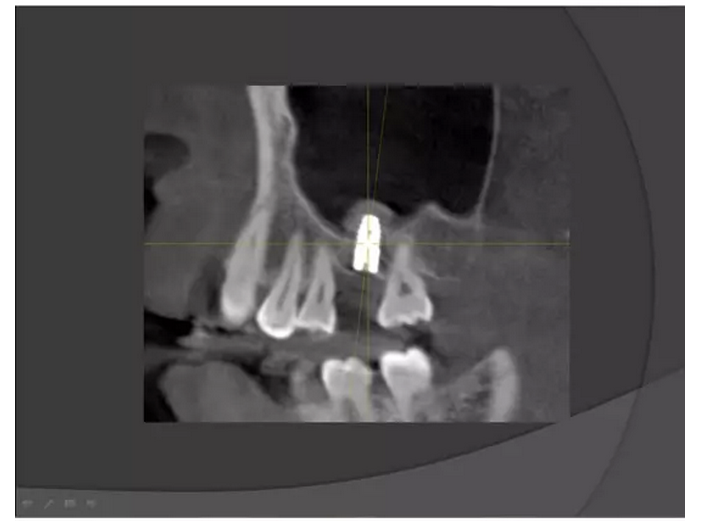

【KQ88口腔網(wǎng)?!可项M竇種植手術(shù)概述——王漢禹

上頜竇種植手術(shù)概述

王漢禹